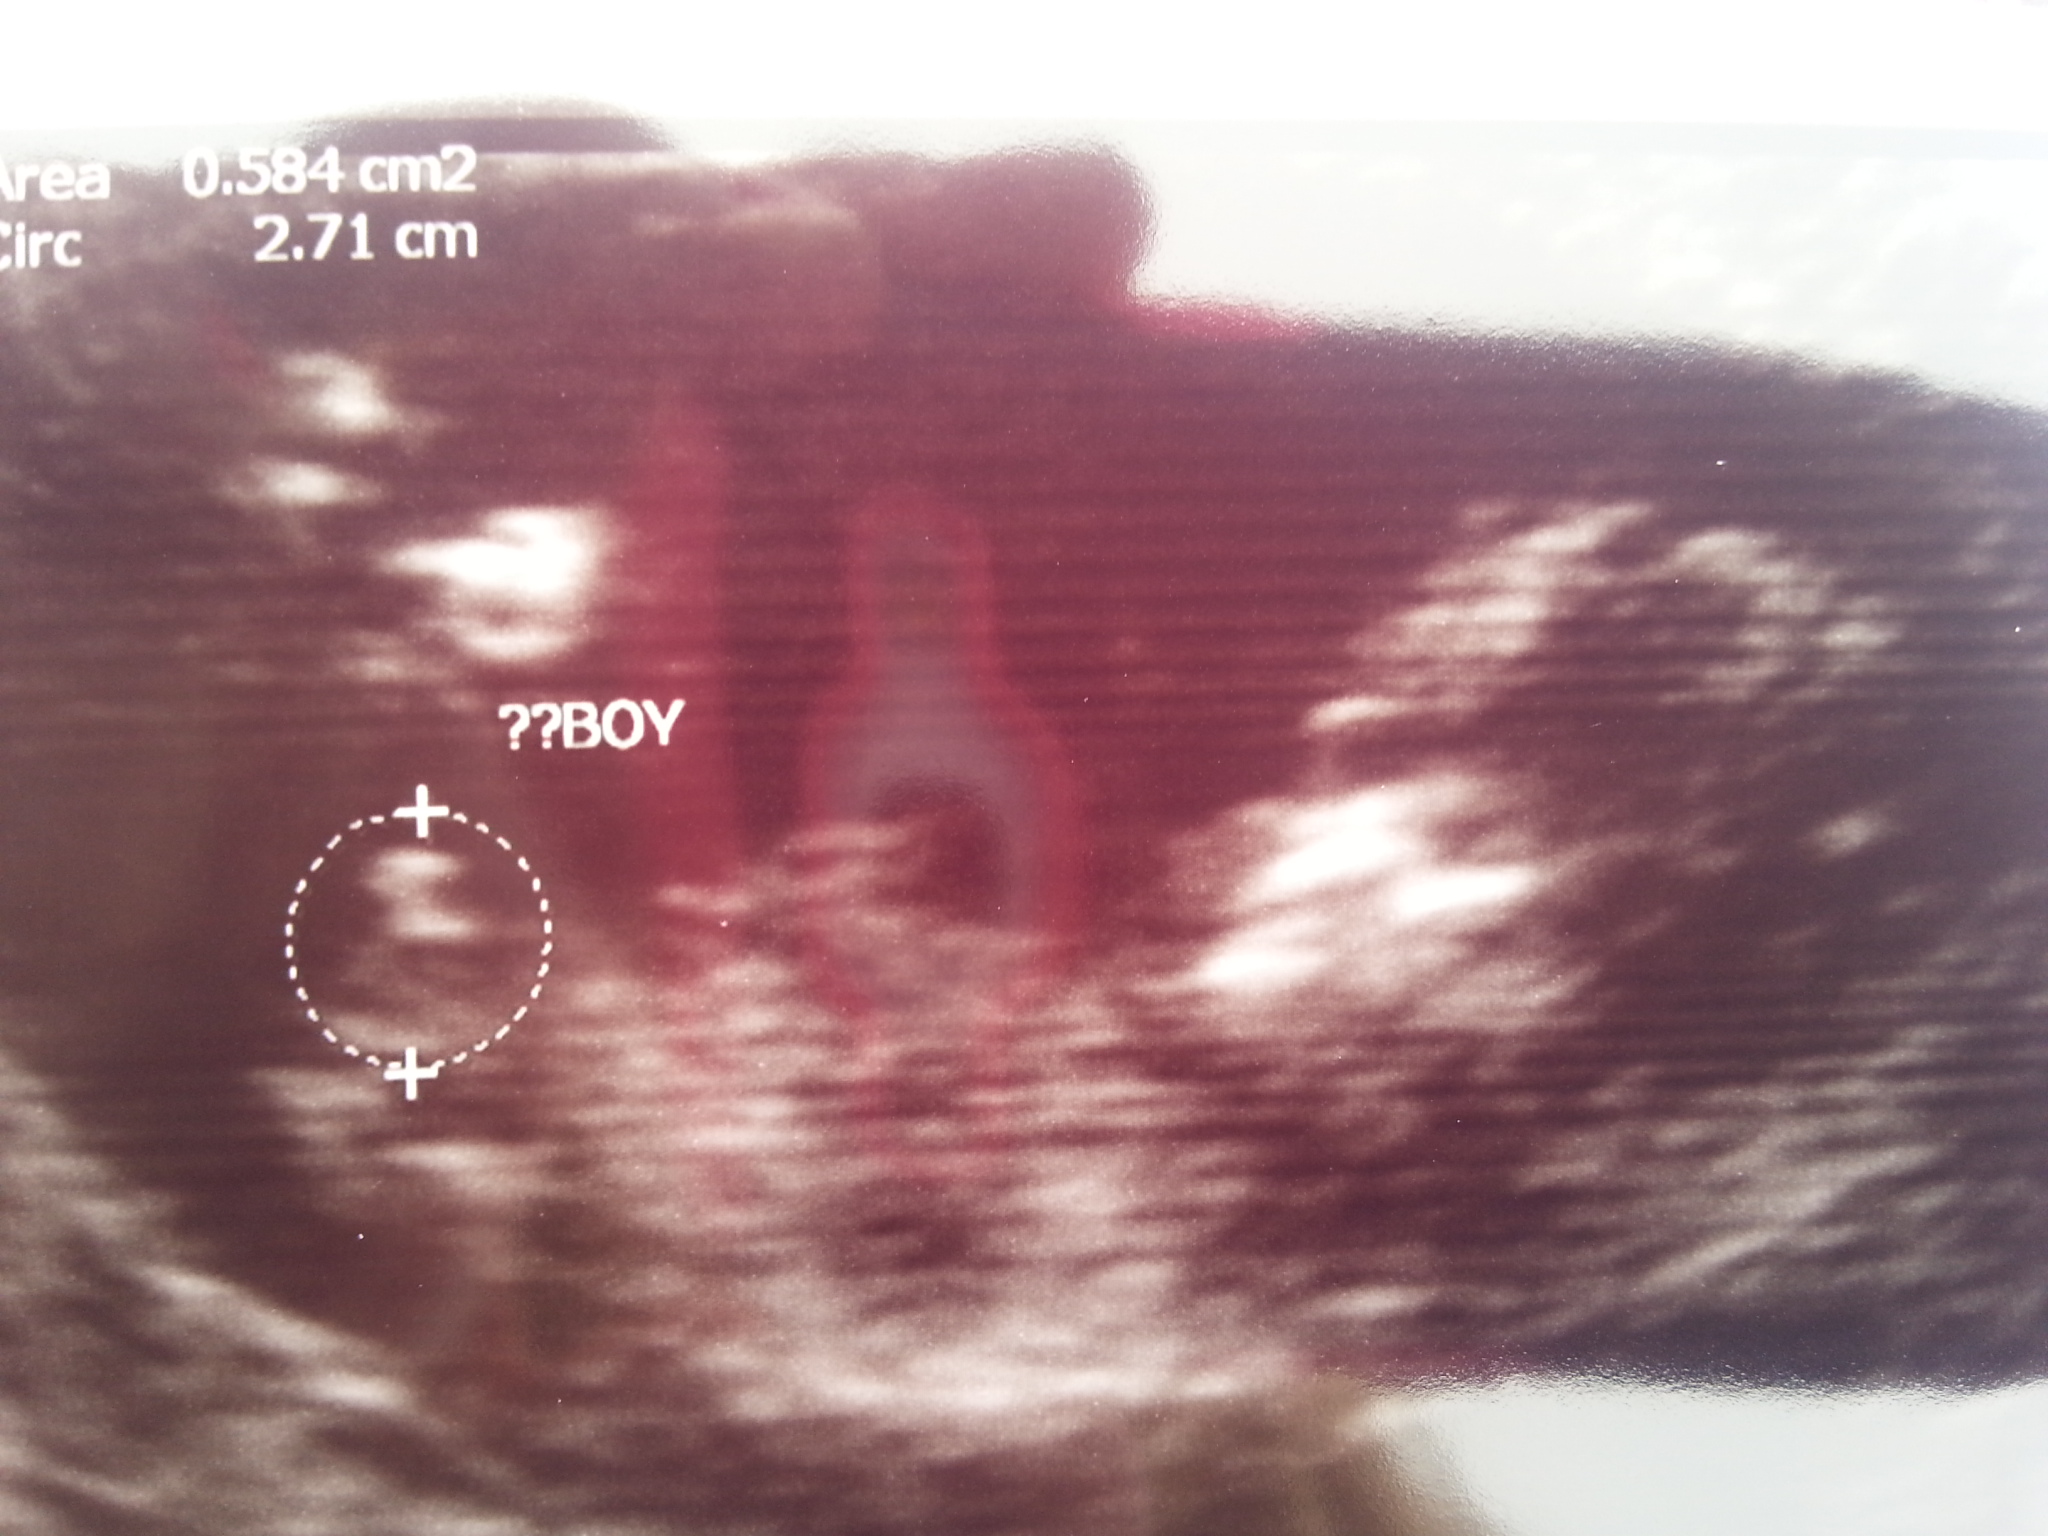

Boy :)

Boy:)

can anyone else see the nub I am convinced it it shown in this picture???

anybody else like to guess please? I am convinced the nub is shown in pic???

boy

I am thinking girl. This is mine at 12w5d not confirmed yet to be boy. The white dot is throwing me off do you have another pic?